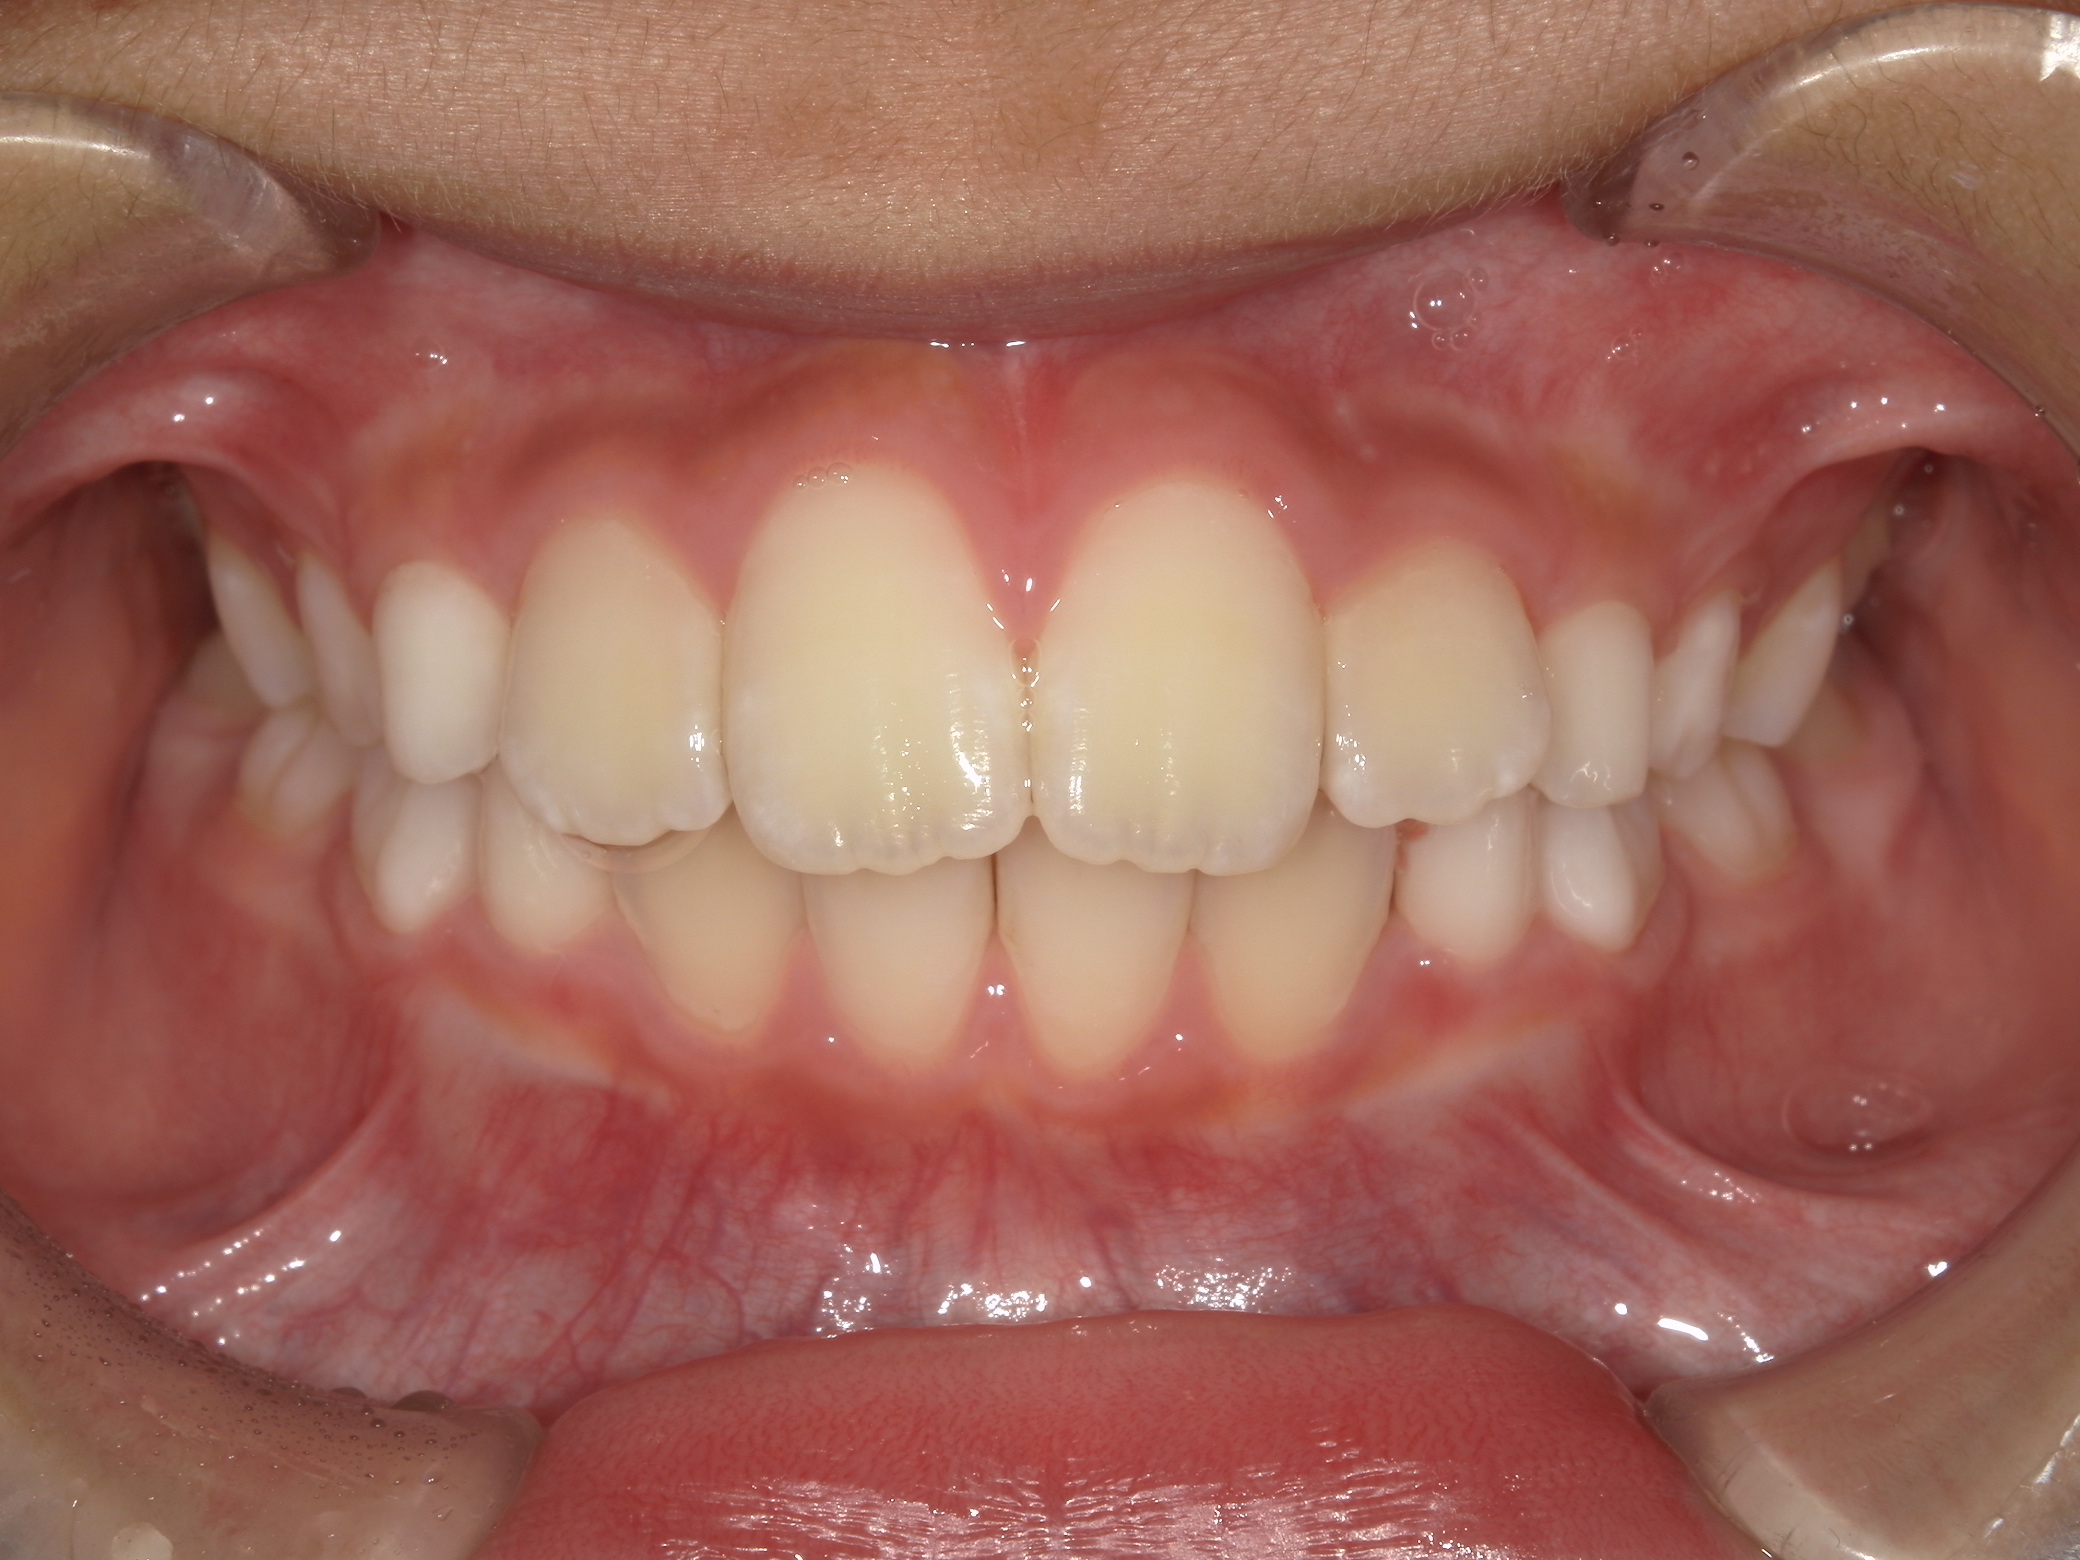

| 年齢・性別 | 8歳9ヶ月の女児 |

|---|---|

| 主訴 | 歯並びの乱れを気にされて来院された患者様です。将来的なスペース不足と歯のねじれ(翼状捻転)が懸念されました。 |

| 治療期間・回数 | 2年10ヶ月・19回 |

| 費用 | 430,000円(税別) |